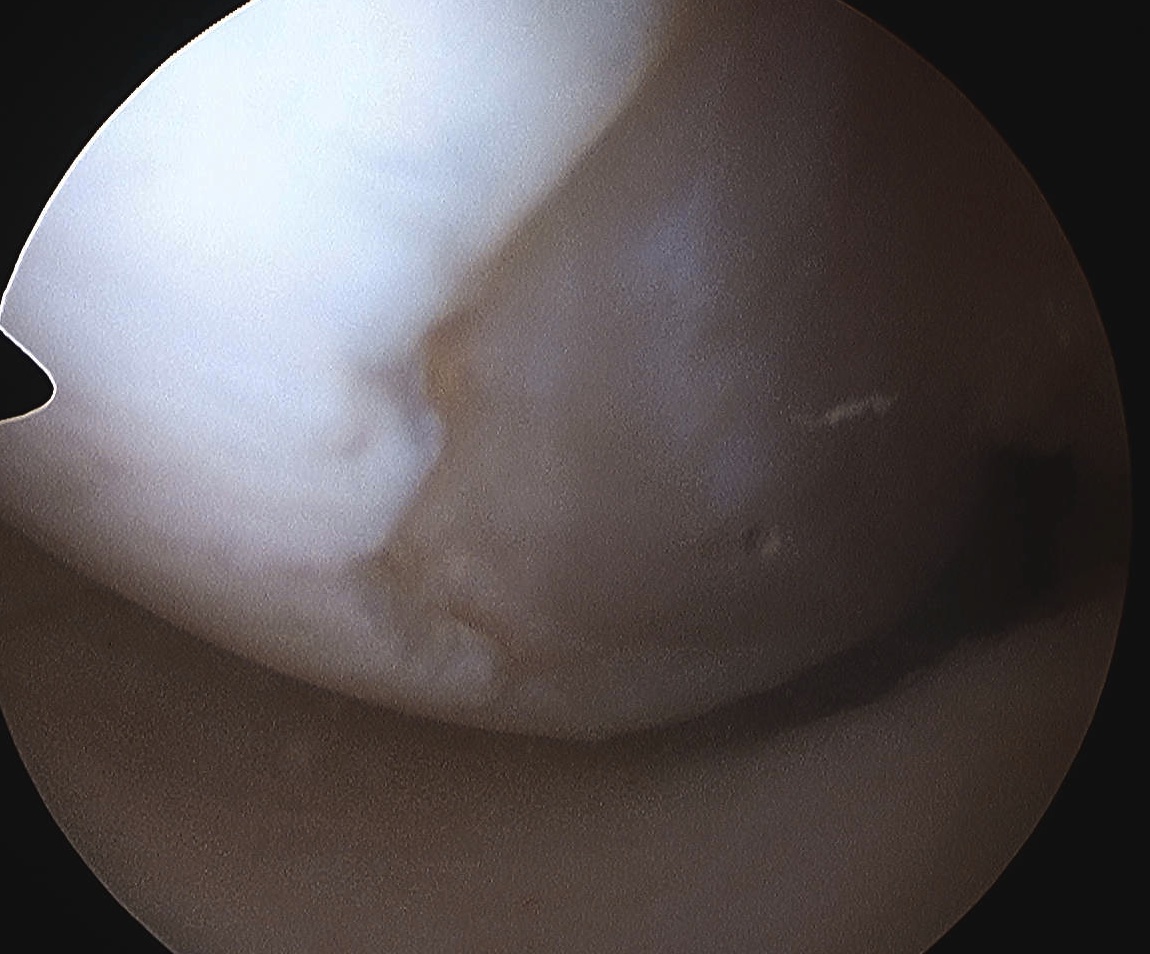

Multi-ligament knee injury (MLKI)

- 2 or more ligaments disrupted

Knee dislocation

- ACL + PCL + one of collaterals